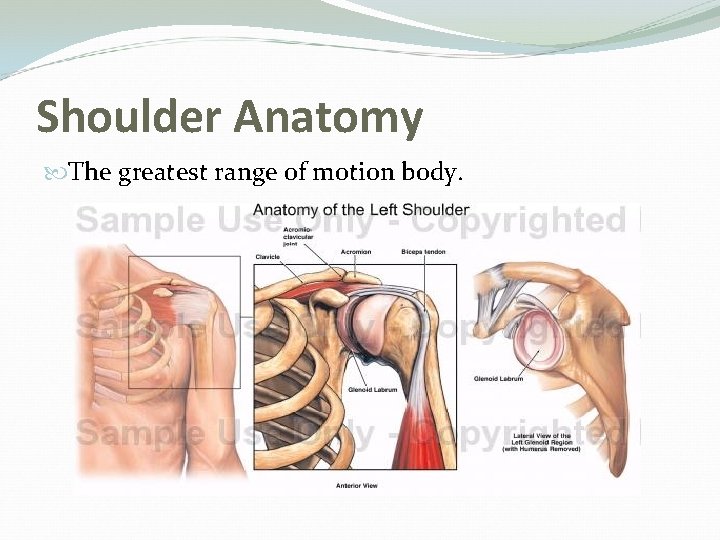

Shoulder Anatomy The greatest range of motion body.